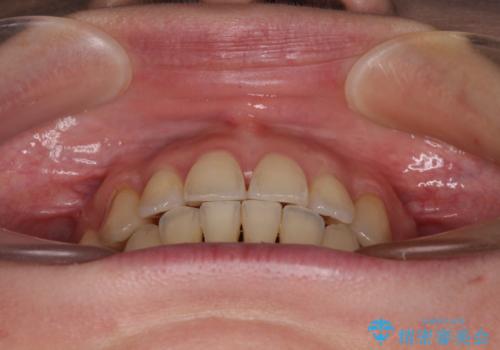

【モニター】上下の八重歯を治したい ワイヤー装置による矯正治療

治療期間全体を通して歯の移動スピードがゆっくりであったので、当初予定よりも1年ほど長い、3年間を要することとなりました。

- 上下前歯のデコボコを気にして来院された患者様です。

デコボコが強いため、非抜歯で矯正をすると出っ歯仕上がりとなるため、上下左右の第一小臼歯4本を抜歯することとしました。